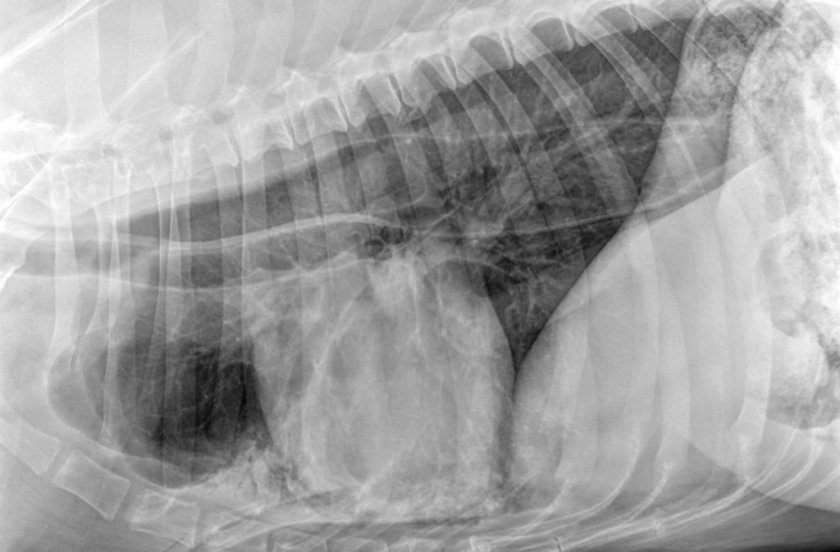

Диагностика аспирационной пневмонии у собак обычно начинается с тщательного физического осмотра ветеринаром. Он прослушивает лёгкие со стетоскопом для выявления аномальных звуков. А также назначает:

- рентгенографию лёгких в 2 проекциях;

Диагноз становится очевиден для врача из последовательности событий. Но для подтверждения делается рентген. Лечение будет начато с кислородной терапии, так как собака будет испытывать трудности с дыханием.